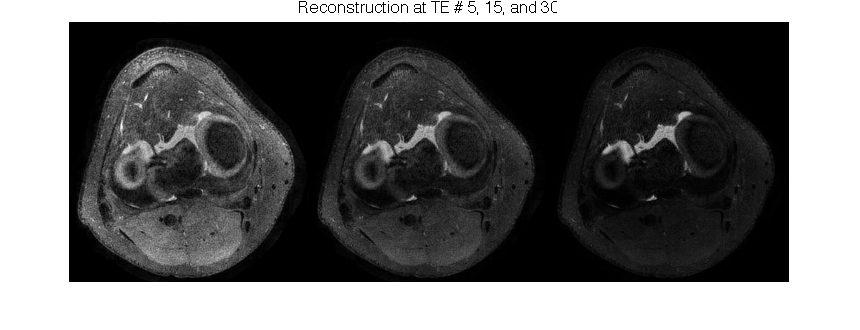

figure(3);

imshow(abs(cat(2, im(:,:,5), im(:,:,15), im(:,:,30))), []);

ftitle('Reconstruction at TE # 5, 15, and 30');